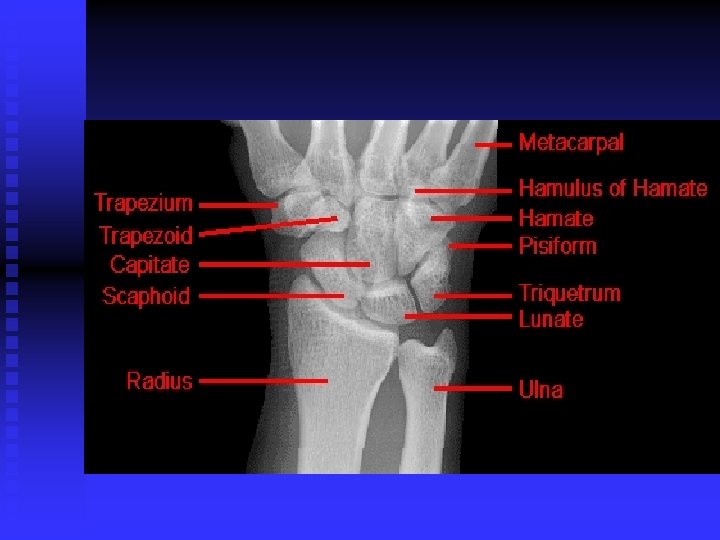

WRIST AND HAND

Carpal Tunnel Syndrome n n Median nerve compression within the carpal tunnel is the most common peripheral nerve entrapment syndrome. Any condition that decreases the cross sectional area of the carpal tunnel or increases the volume of its contents may cause the pathology. EX: lunate dislocation; distal radius fracture, sustained flexion or extension postures, fluid retention, synovitis